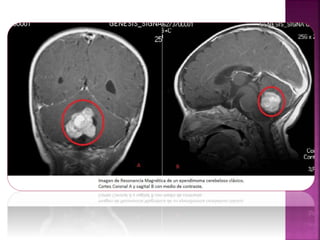

Los tumores decerebro y de médula espinal son los tumores sólidos más frecuentes en los niños. Algunos tumores son benignos y los niños son curados con una cirugía. Sin embargo, en el caso de los malignos, dada la dificultad en el diagnóstico y en el tratamiento, no se ha avanzado tanto en su cura como en otros tipos de cáncer infantil. Su tratamiento en general incluye cirugía más otras terapéuticas, como quimioterapia y radioterapia.